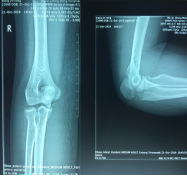

手法整复桡骨远端骨折、踝关节骨折、尺骨骨折、掌骨骨折、指骨骨折、跖骨骨折及肩关节脱位、桡骨小头半脱位等各类骨折脱位十余例,行小夹板固定及石膏托外固定十余例。